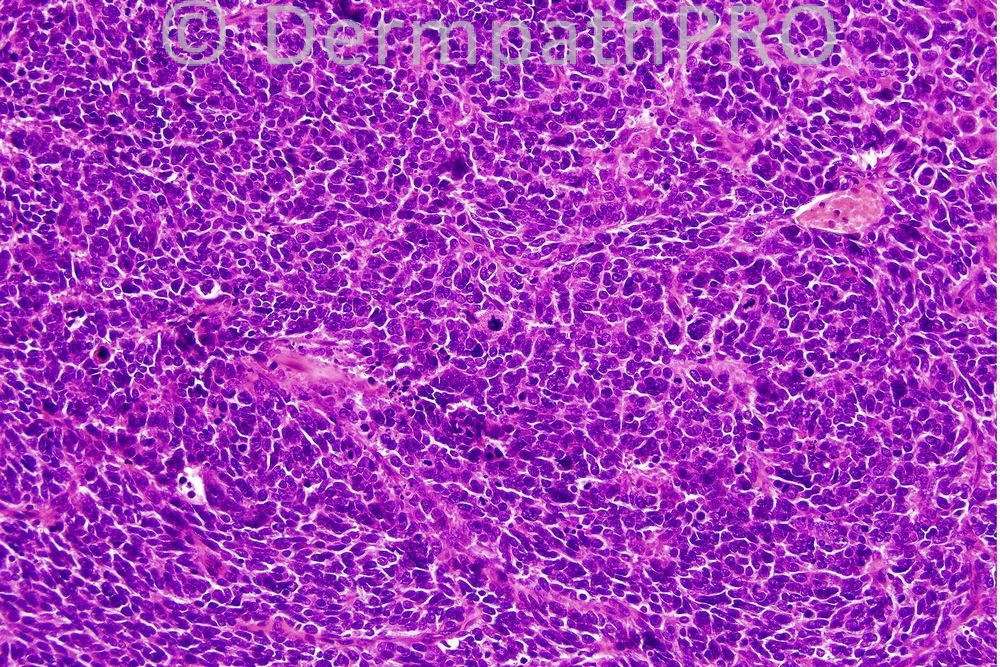

Female 78 years, nodule on neck

Most of you got the correct diagnosis. Primary cutaneous MCC with squamous differentiation. The diagnosis was confirmed with immunohistochemistry. Have a great weekend.

Merkel cell carcinoma with squamous differentiation

Merkel cell carcinoma

B cell lymphoma vs Merkel cell carcinoma